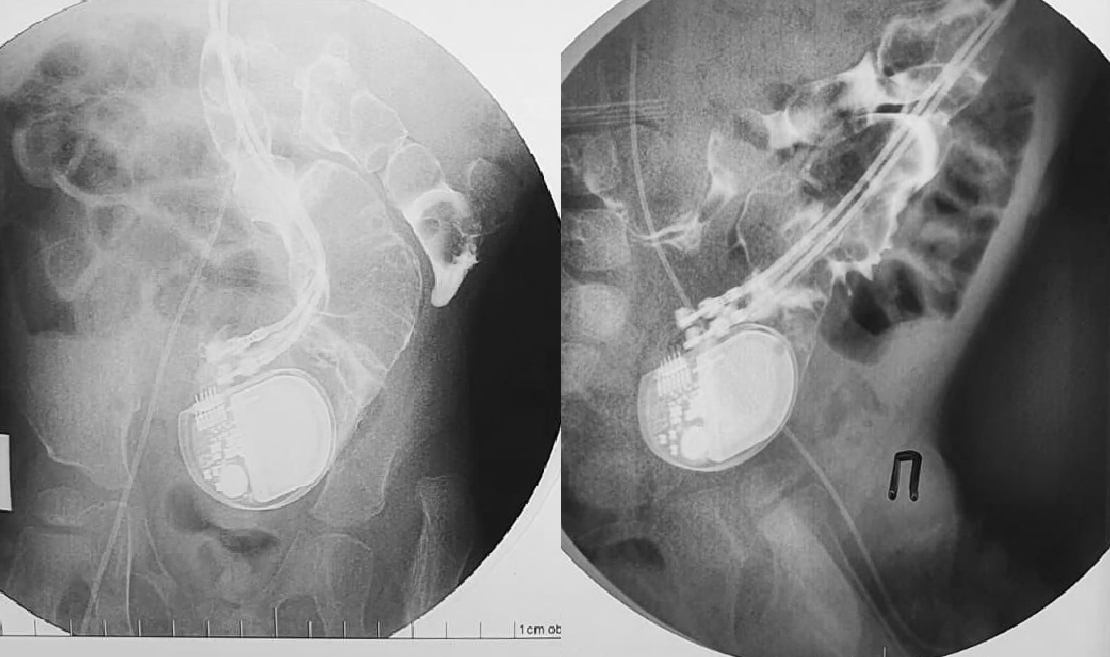

На рентгенографии подтвердилось то, что казалось невероятным: устройство не только сумело мигрировать в брюшную полость, преодолев барьер из мышцы и брюшной стенки, но и проникло непосредственно в кишечник, продолжая при этом исправно работать и задавать необходимый ритм сердцу.

Дальнейшие исследования показали, что местом входа в кишечник стала сигмовидная кишка, по ней кардиостимулятор продвинулся дальше, но окончательно покинуть организм не мог - мешали электроды и проводки, которые тянулись за ним от сердца. Отрыв или инфицирование электродов могли привести к гибели от сердечной патологии, в то же время сквозное повреждение брюшной и кишечной стенок уже привело к образованию кишечного свища, возникла закупорка кишечника.